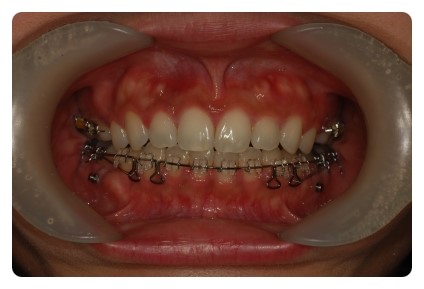

치아교정 전후 사진을 비교해보니 쏘옥 들어간 앞니 ~~~

보다 더 놀라운건 교합 !!

상하악이 거의 맞물리고 잇엇는데

지금은 윗니가 아랫니를 싸악 ~~~ 덮는 이쁜 모양새 ~~~

덧니교정을 시작한지 벌써 2년이라며 징징대긴 햇지만

이뻐지고잇는 치아들을 보니 금새 기분좋아짐 ㅋㅋ